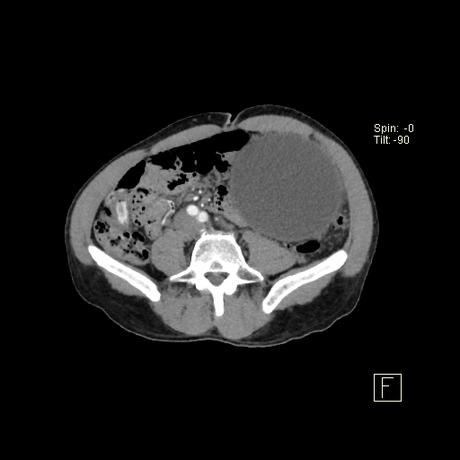

producen por la alteración de la estructura del conducto pancreático con la consiguiente pérdida y acumulación de jugo pancreático que da lugar a una necrosis grasa hemorrágica. No están revestidos por epitelio (por lo tanto, “pseudoquistes”), sino que una reacción inflamatoria grave da como resultado la encapsulación del quiste por tejido de granulación fibrosado. Esto suele tardar de 4 a 6 semanas 8,9 . En aproximadamente el 50% de los casos, el quiste conserva una comunicación con el conducto pancreático 2 . Estos quistes son más problemáticos de tratar y es más probable que reaparezcan.